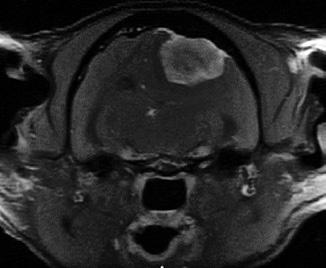

“Mikey stopped attacking his siblings and started stumbling around, walking in circles and staring at the wall,” Stacy recalls. Totally out of Mikey’s character, Stacy and Drew decided to have him checked out at OSU’s Veterinary Medical Hospital. Dr. Shane Lyon, small animal internal medicine, first saw Mikey and ordered an MRI.

“The MRI showed a huge mass on Mikey’s brain,” says Dr. Mark Rochat, former small animal surgery section chief. “It was about the size of a large grape and was pressing on the cat’s brain, which basically affected Mikey’s behavior.”

Mikey was not a fan of the cone he had to wear after his brain surgery at OSU’s Veterinary Medical Hospital.

Mikey’s surgery took about an hour. “This type of tumor is one of the easier types to deal with. Mikey came through surgery without any lasting problems,” adds Rochat — but with another change of behavior.